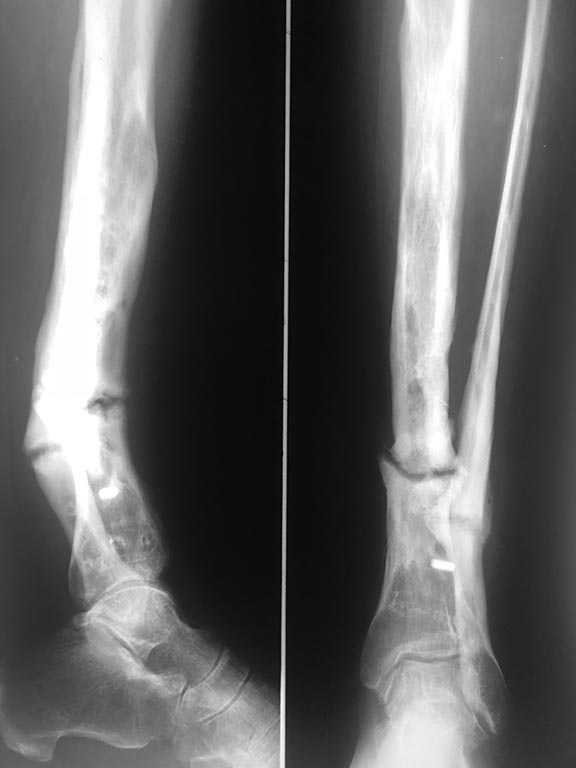

Ложный сустав костей голени

Обратилась пациентка с тугоподвижным ложным суставом костей правой голени в н/3 с антекурвационной деформацией и укорочением.

Кратко по анамнезу- в 2011г. закрытый перелом костей правой голени,выполнен накостный МОС, осложнение -нагноение в раннем п/о периоде, Удаление м/к и ЧКДО аппаратом Илизарова. Далее -резекция большеберцовый кости в процессе секвестрнекрэтомии,перемонтаж АВФ с попыткой билокального ЧКДО,далее , уже в 2014г. - открытое вмешательство- костная пластика и накостный МОС, через 1 год закончилось удалением м/к по поводу рецидивирующих свищей.

В настоящее время тугой ложный сустав , деформация с укорочением 3-4см.; свищей в течение 2.5 лет не было.Вопрос-можно ли направить в пациентку в один из федеральных центров травматологии? какой?